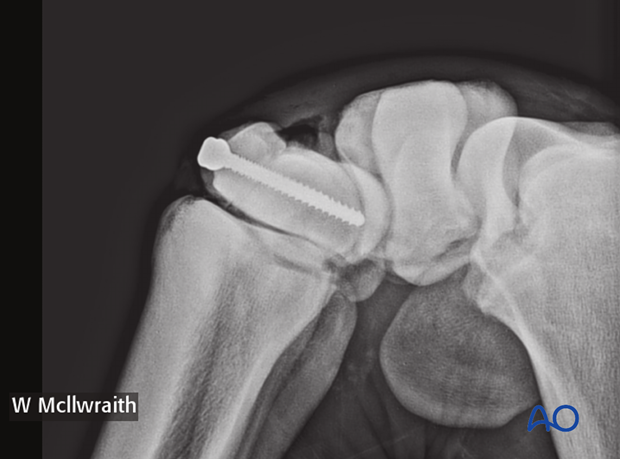

A flexed LM and ...

…skyline radiographic views are taken to provide the proximal-distal location of the lag screw.

Based on the radiographs two stab incisions are placed over the dorsal aspect of the radial and the intermediate facets respectively. Their positioning is based on radiographs of spinal needle placement.

Pearl: Use two fingers and thumb when doing final tightening, thereby avoiding excessive torque and potential breaking of screw head. Intraoperative radiographs are taken to confirm screw length and correct positioning.

Intraoperative radiographs are taken to confirm screw length and correct positioning.